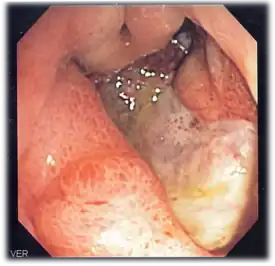

Endoscopic image of a posterior wall duodenal ulcer with a clean base, which is a common cause of upper GI hemorrhage.

Endoscopic image of a posterior wall duodenal ulcer with a clean base, which is a common cause of upper GI hemorrhage.